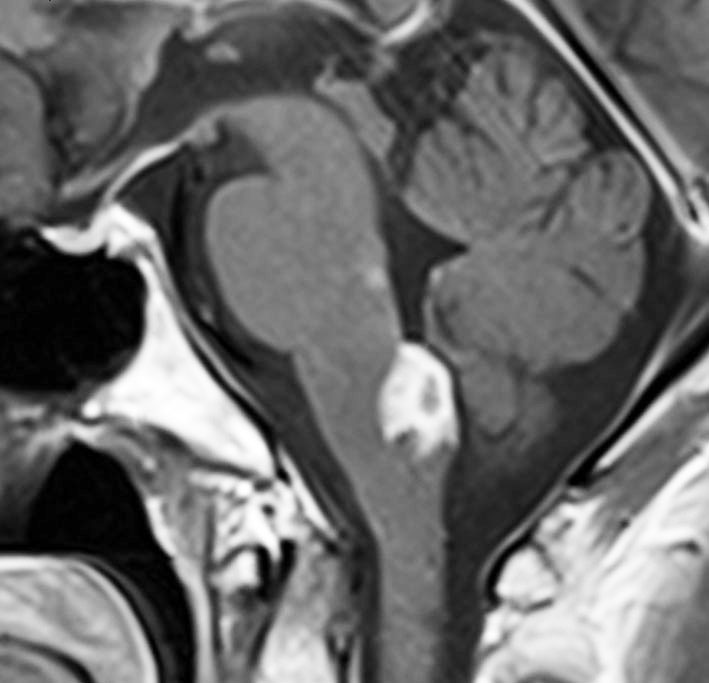

10歳くらいから身長の伸びが遅くなって,12歳で食欲低下と体重減少がありました。左のMRIはガドリニウム造影MRIで,視床下部と下垂体を侵す神経下垂体ジャーミノーマです。CTでは小さな石灰化(白い点)がみえます。CT検査は不必要なものでした。

尿崩症にて発症した2年後にようやく小さなneurohypophyseal germinomaを発見された9歳女児例です。術前のT1強調画像では下垂体後葉のbrightnessが消失し,下垂体柄が腫大しています(左側)。ガドリニウムで腫瘍部分が増強されますが前葉よりは低信号となっています(右側)。経蝶形骨洞生検術で確定診断を得た後に,シスプラチンとエトポシドを1コース投与したところ腫瘍は完全消失しました。3コース後に24Gy12分割の放射線治療を加え再発はありません。残っていた下垂体前葉機能は治療後に少し改善しました。生検術では,トルコ鞍底を開けて下垂体後葉の下部を目標にして小さな組織採取をします。GHDがあっても前葉にはmassとしての腫瘍が無いと考えた方がいいでしょう。